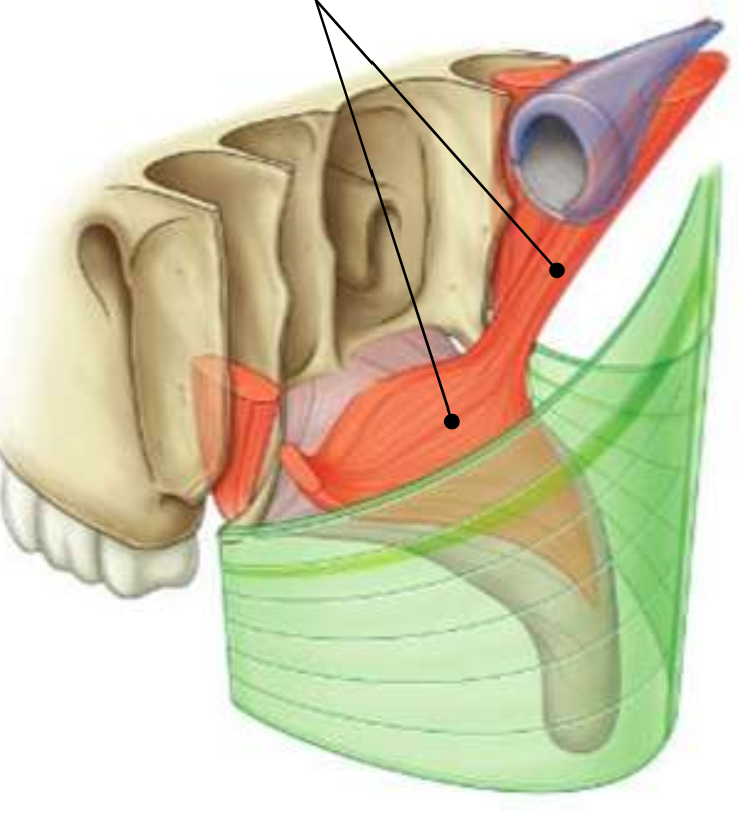

What muscle is this?

palatopharyngeus

What are the attachments of this muscle?

upper surface of palatine aponeurosis → deep pharyngeal wall

What is the function of this muscle?

closes the oropharyngeal isthmus by depressing the palate